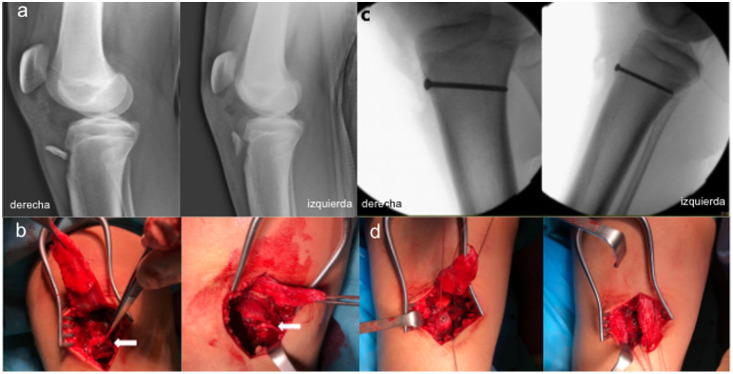

胫骨前结节骨折撕脱是一种不常见的损伤。同时伴有髌骨断裂的情况更是罕见。我们报告了一名 14 岁男性患者的病例,他双侧胫骨前结节骨折,同时伴有双侧髌腱完全断裂。青春期、运动量和高体重指数可能是造成这种并发双侧损伤的原因。两处损伤均采用一期修复手术进行治疗,使用插管皮质螺钉对胫骨结节进行切开复位和内固定,并按照克拉科夫技术对肌腱进行初步缝合。据作者所知,迄今为止还没有其他文献报道过双侧均有病变的病例。

Anterior tibial tuberosity fracture avulsion is an uncommon injury. A concomitant patellar rupture is even more scarcely encountered. We report the case of a 14-year-old male patient who suffered bilateral anterior tuberosity fractures with concomitant bilateral complete patellar tendon rupture. Adolescence, athletic activity, and high BMI may have contributed to this concomitant bilateral injury. Both lesions were treated in a one-stage repair surgery, performing an open reduction and internal fixation of the tibial tuberosity with a cannulated cortical screw and a primary tendon suture following the Krakow technique. To the authors' knowledge, no other cases of bilateral presentation of both lesions have been reported so far in the literature.